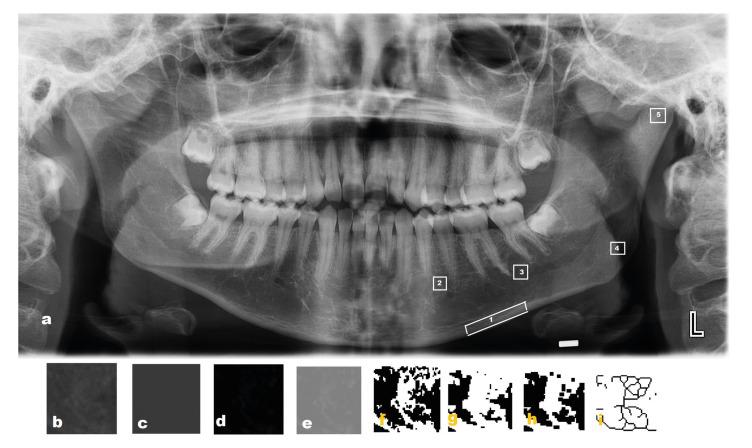

The study included 80 patients (with 40 patients each of ß-TM and control). The mandibular cortical width (MCW), panoramic mandibular index (PMI), mandibular cortical index (MCI), and simple visual estimation (SVE) were evaluated, and an FD analysis of five regions of interest (ROIs) (ROI 1: in basal cortical bone; ROI 2: in premolar region; ROI 3: in molar region; ROI 4: in angulus mandible and ROI 5: in condyle region) was obtained in all DPRIs. Quantitative variables were analyzed using the student's t-test , Kruskal-Wallis and Mann-Whitney U tests.

该研究纳入了 80 名患者(每组 40 名ß-TM 和对照组)。评估了下颌骨皮质宽度(MCW)、全景下颌指数(PMI)、下颌皮质指数(MCI)和简单视觉估计(SVE),并在所有 DPRIs 中获得了五个感兴趣区域(ROI)的 FD 分析(ROI1:在基底皮质骨中;ROI2:在前磨牙区;ROI3:在磨牙区;ROI4:在下颌角区;ROI5:在髁突区)。使用学生 t 检验、Kruskal-Wallis 和 Mann-Whitney U 检验分析定量变量。